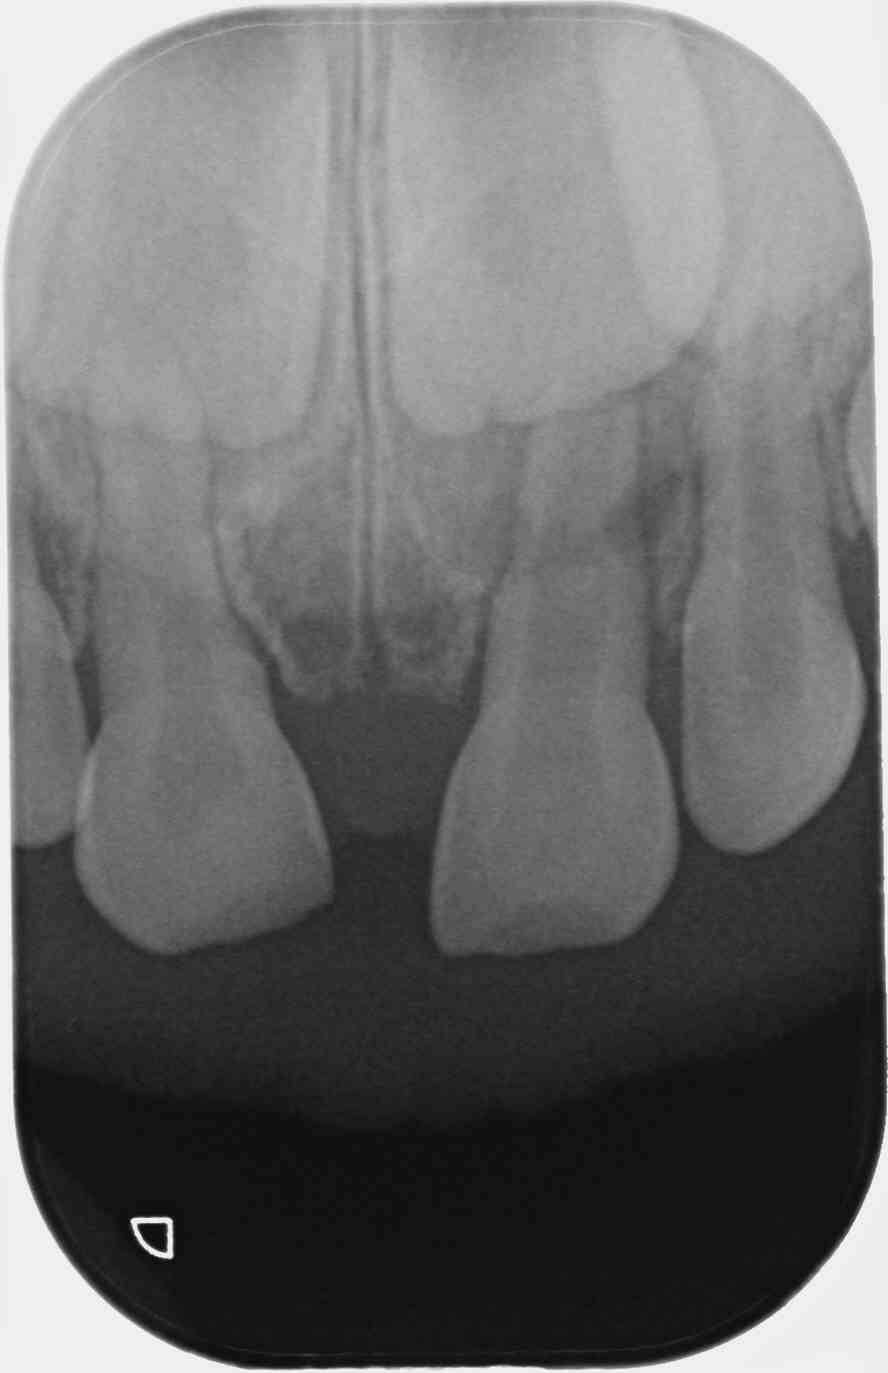

Garçon de 2 ans 11 mois, chute sur la face, peu de douleur, pas de mobilité, saignement sillon de 51.

Je ne vois rien de particulier à la radio.

Diagnostic de concussion je pense,

Il faudrait l'avis d'un pédo, mais en ce qui me concerne dans ce cas je fais une simple surveillance tous les 6 mois, y compris radiographique. Ce genre de trauma est extrêmement fréquent, les minéralisations ou nécrose des incisives lactéales consécutives sont aussi forcément très fréquentes. Les complications sont rares car la nature est plutôt bien faite sur ce coup là. La complication la plus évidente est un réveil infectieux aigu ou l'apparition d'une parulie (fistule) à l'apex, la plus vicieuse est la formation d'un granulome/kyste sans aucun symptôme clinique, avec déviation du germe de la centrale, indiquant l'avulsion de la dent lactéale concernée. Vu une fois en 12 ans.

Trauma à 2 ans, rvg à l'âge de 3 ans puis 5 ans (avulsion indiquée) puis à 7 ans.